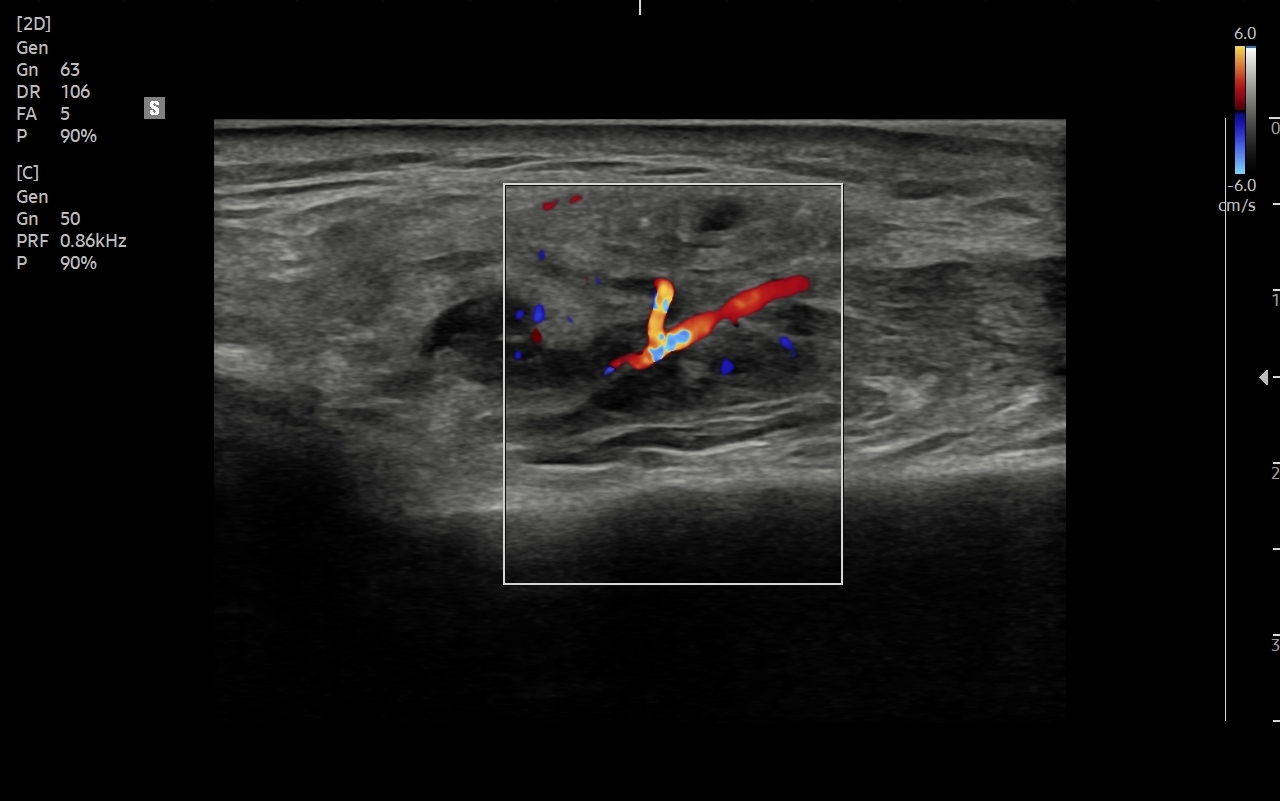

Pacjenci ze skierowaniem na badanie USG ślinianek zgłaszają się do Pracowni zwykle w przypadku dolegliwości subiektywnych bądź obiektywnych zlokalizowanych w okolicy żuchwy i górnych partii szyi. Należy jednakże mieć na uwadze, że patologie umiejscowione w wymienionych obszarach nie zawsze odpowiadają chorobom ślinianek, a mogą dotyczyć np. węzłów chłonnych, migdałków, czy innych tkanek miękkich szyi. USG to podstawowe badanie obrazowe ślinianek. Jest procedurą bezpieczną i dokładną, a w Pracowni dr Szczepańskiego ślinianki oceniane są nowoczesną metodą MPUS (multiparametryczne USG) z zastosowaniem trybów mikrounaczynienia i elastografii. W przypadku konieczności oceny głębokich części ślinianek przyusznych albo zaplanowania operacji w obrębie szyi wykonuje się tomografię komputerową lub rezonans magnetyczny szyi.